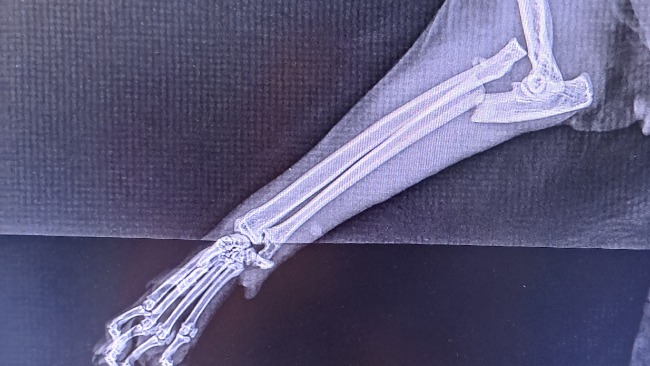

Witam, wracając dzisiaj do domu z pracy zastałam mojego kotka z łapka która utknęła mu w uchylonym oknie, nie mam pojęcia co mojego urwisa tak zaciekawiło, że postanowił pchać łapki przez okno, nie wiadomo jak długo biedny tam tkwił. Po wizycie u weterynarza okazuje się, że jest złamana w łokciu oraz zwichnięcie i czeka go operacja. Wraz z Diomedesem prosimy o wszelką pomoc w uzbieraniu na operacje. Będę wdzięczna za każdą pomoc.